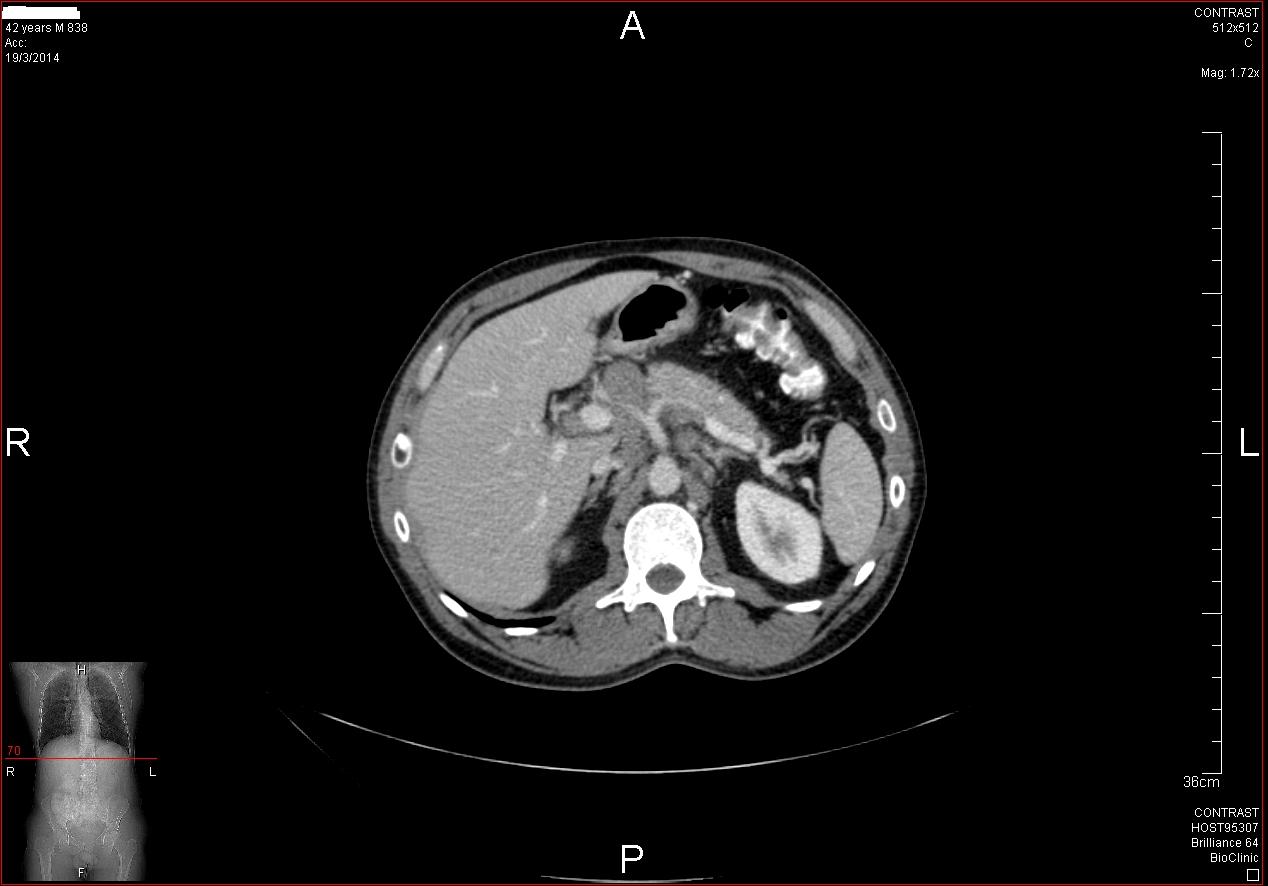

Άνδρας 43 ετών, χωρίς προηγούμενο ατομικό ή οικογενειακό ιστορικό, εμφάνισε επίμονους εμέτους και επιγαστραλγία. Υποβλήθηκε σε αξονική τομογραφία θώρακος, άνω και κάτω κοιλίας από το θεράποντα ιατρό του που έδειξε διάχυτη θωρακική και κοιλιακή λεμφαδενοπάθεια, με διογκωμένους λεμφαδένες στον υποτροπιδικό χώρο, στον αλλήρειο τρίποδα, στον ηπατοδωδεκαδακτυλικό σύνδεσμο και πέριξ του παγκρέατος. Ο ασθενής παραπέμφθηκε για ενδοσκοπικό υπέρηχο και λήψη βιοψιών από τους λεμφαδένες. Έγινε βιοψία με ειδική βελόνα για λήψη ιστοτεμαχίων (Pro-Core 19g) από λεμφαδένες σε 3 διαφορετικές θέσεις (υποτροπιδικά, αλληρείου τρίποδα και ηπατοδωδεκαδακτυλικού συνδέσμου). Η ιστολογική εξέταση και ο ανοσοϊστοχημικός έλεγχος έδειξε αδενοκαρκίνωμα χαμηλής διαφοροποίησης χωρίς θετικότητα στις επιμέρους, ειδικές χρώσεις. Ο ενδοσκοπικός έλεγχος του πεπτικού επιβεβαίωσε την ύπαρξη νεο-εξεργασίας στην ηπατική καμπή του παχέος εντέρου που ιστολογικά ήταν ένα αδενοκαρκίνωμα χαμηλής διαφοροποίησης. Ο ασθενής παραπέμφθηκε για προεγχειρητική χημειοθεραπεία και χειρουργική αντιμετώπιση.

CT: υποτροπιδικός λεμφαδένας

CT: λεμφαδένας αλληρείου τρίποδα

CT: λεμφαδένας ηπατοδωδεκαδακτυλικού συνδέσμουνδεσμο